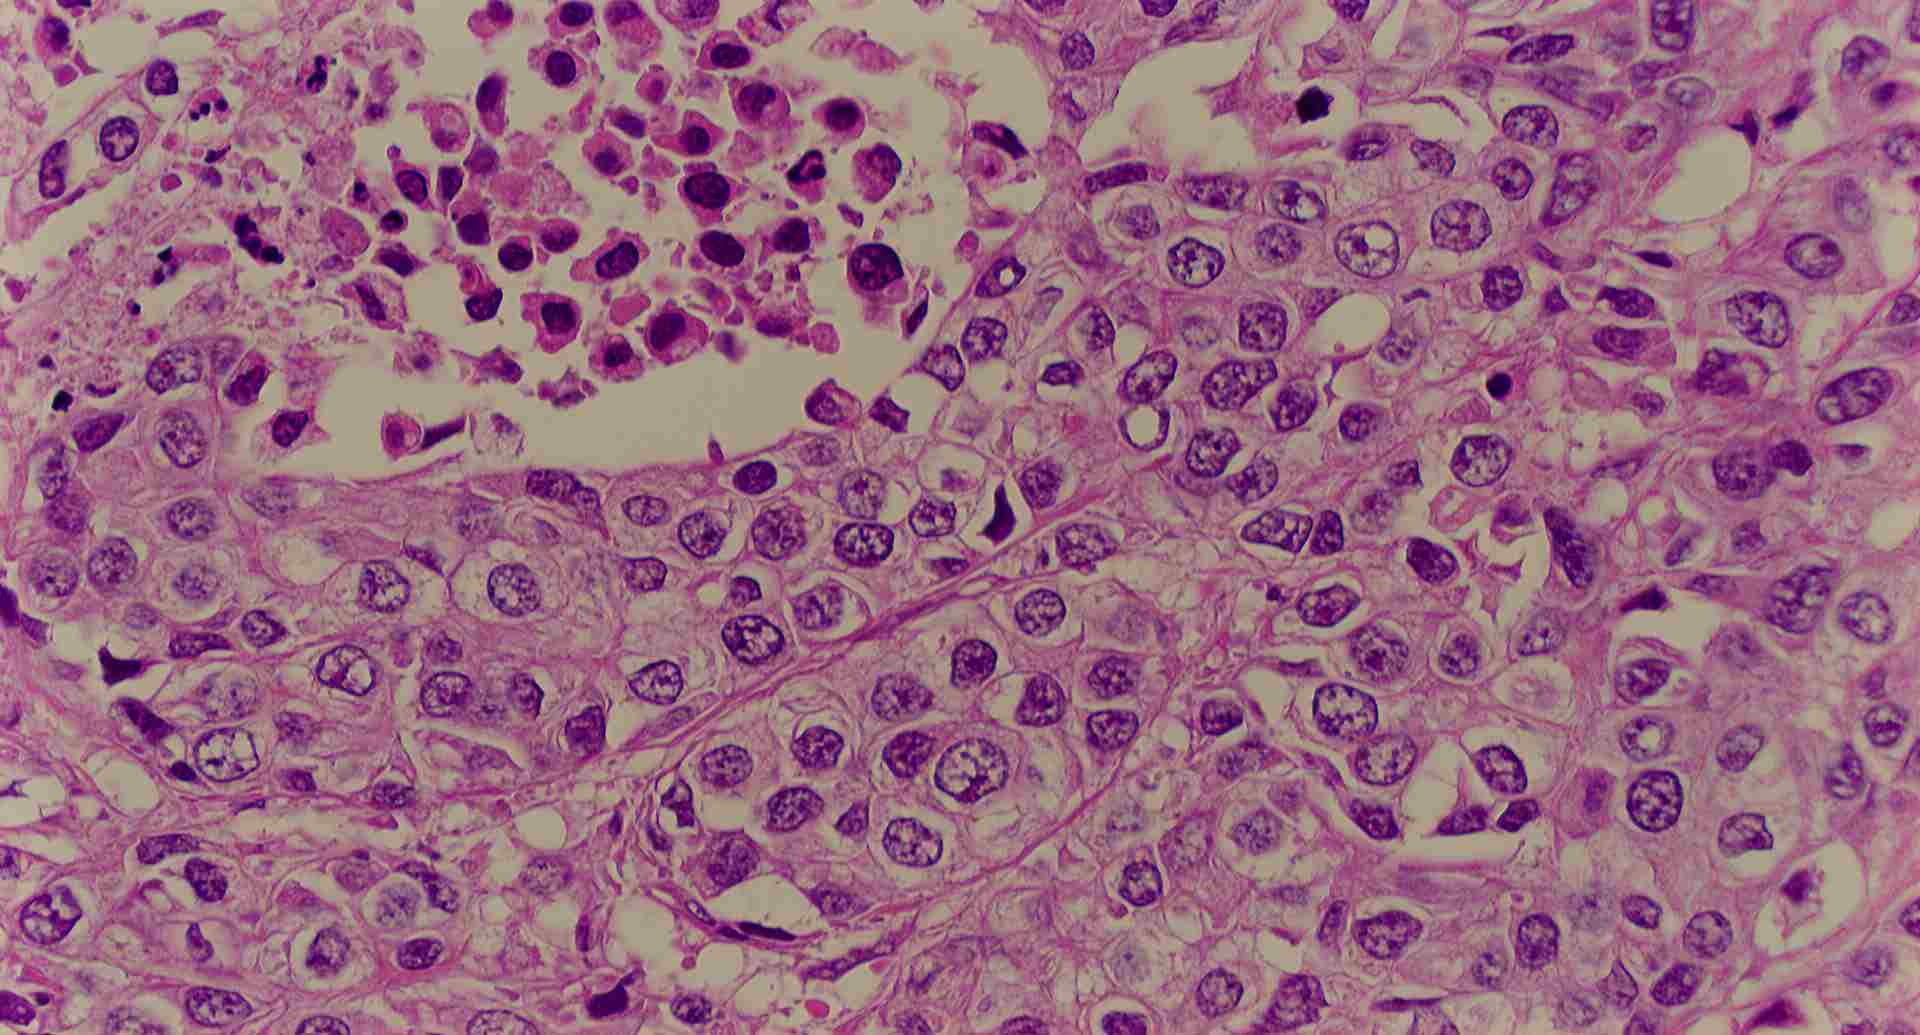

標本8